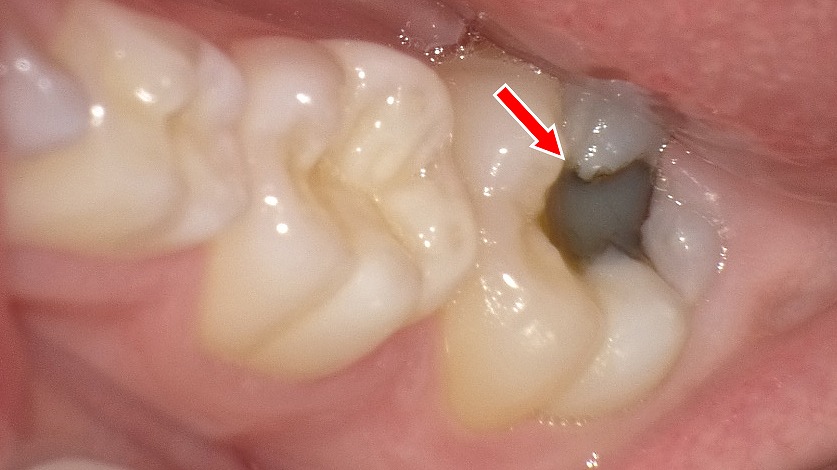

🕳 深い溝と磨き残しのリスク

6歳臼歯のかみ合わせ部分には、深くて複雑な溝(裂溝)が存在します。

🌀 この構造が原因で…

- 食べかすやプラークが溜まりやすい

- 通常の歯ブラシでは溝の奥まで届きにくい

- 汚れが残ったままになり、虫歯が発生しやすい

🛡 有効な予防策:

- シーラント処置(溝を樹脂で埋める予防法)

- タフトブラシなどの補助的な清掃器具の活用

- 親による仕上げ磨きで奥歯の溝を重点的にケア

🧼 気づかれにくい場所に生えるリスク

6歳臼歯は、乳歯のさらに奥に生えてくるため、保護者も子ども自身も気づきにくい歯です。

🙈 この「気づかれにくさ」が招く問題:

- 生え始めの時期に磨き残しが多発

- 歯ぐきに一部埋まっていることで歯ブラシが届かない

- 虫歯や歯肉炎(萌出性歯肉炎)が気づかないうちに進行

📌 対応策としては、

- 5歳半ごろから奥歯の生え方を観察

- 歯が見えてきたら夜の仕上げ磨きで必ず奥まで確認

- 歯科医院での早期チェック・フッ素塗布・シーラントが効果的です